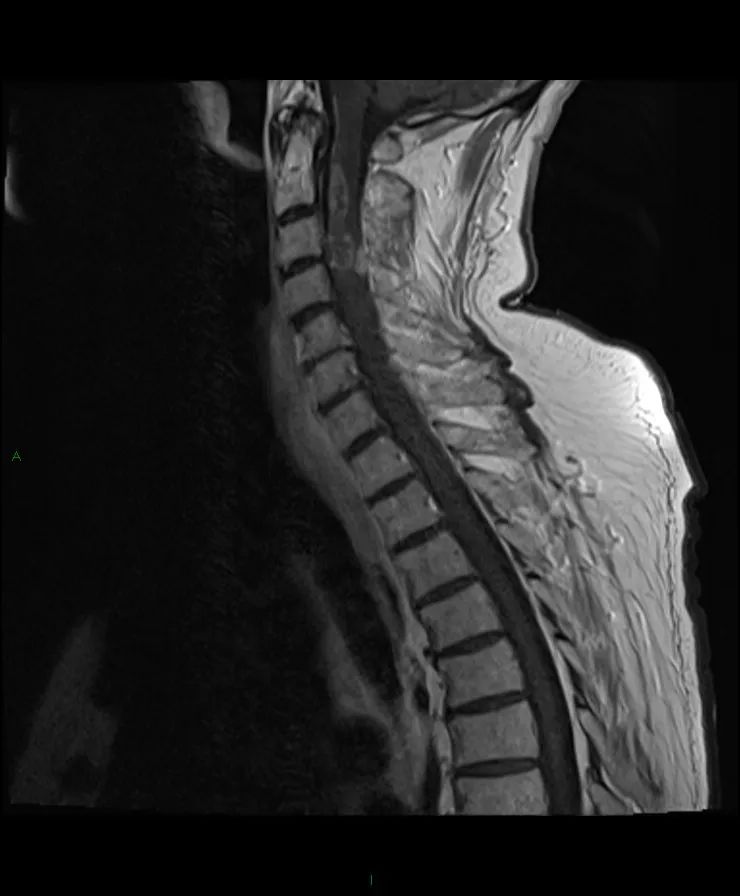

【病例】脊髓星形细胞瘤1例MR影像-4

颈脊髓在C2和T1之间肿块,T1等信号,T2高信号,不规则的非均匀强化。